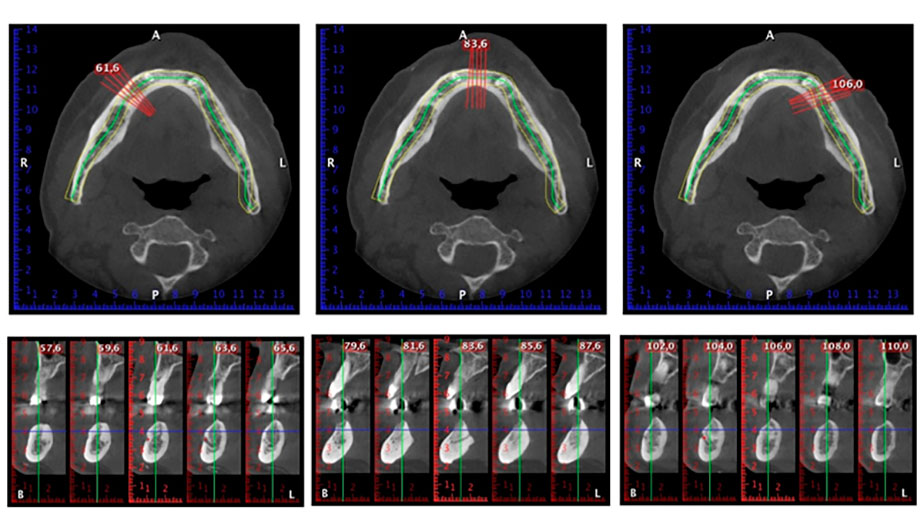

A three-dimensional cone beam computed tomography scan (CBCT, Planmeca) was performed to aid planning and minimize risks. This revealed that the quality and quantity of the available bone were sufficient for the surgery and immediate restoration using the Fast & Fixed method. Following the protocol for this concept, the implants are inserted at 35, 32, 42 and 45. Angling the distal implants by up to 45° shifts the emergence profile to posterior and generates a larger support polygon (Fig. 3).

Fast & Fixed method